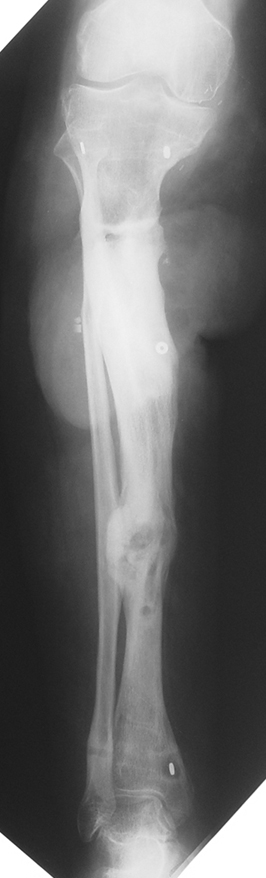

Case 1